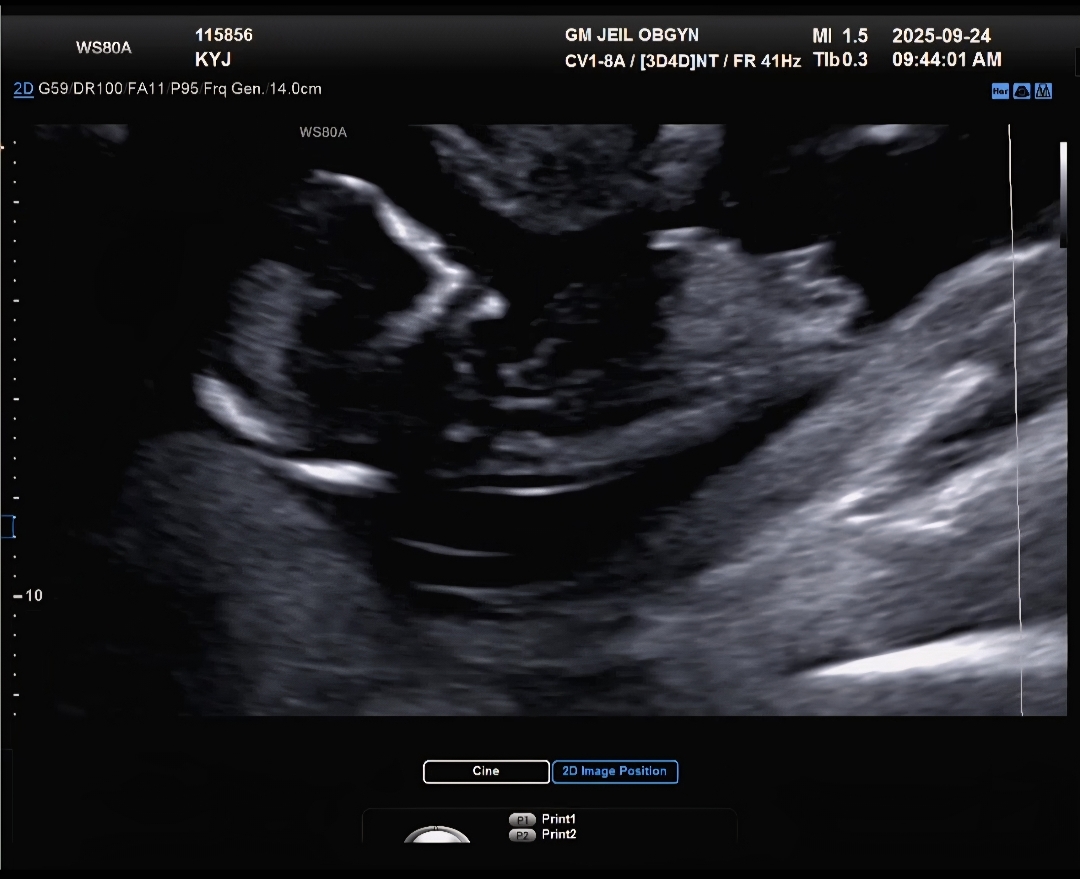

12주5일차입니다 각도법 투표한번씩 부탁드려요🙏❤️